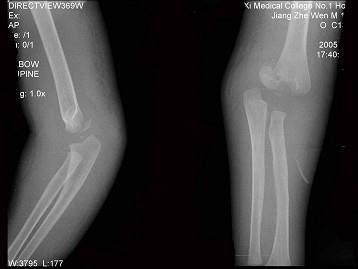

问题 女,1岁10个月,右肘部外伤,如图所示,最佳的诊断为?(?)

选项 A.全骺分离 B.肱骨髁上骨折 C.肱骨髁上骨折并肘关节脱位 D.内上髁骨骺损伤 E.内上髁骨骺损伤并肘关节脱位

答案 A